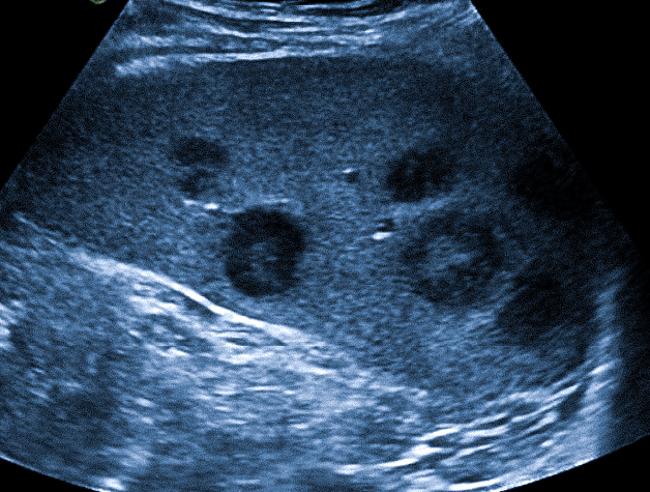

С точки зрения диагностики, аксиллярные лимфоузлы с такими признаками требуют тщательного изучения. Патологические изменения в лимфоузлах могут сигнализировать о развитии серьезных заболеваний, таких как лимфома или метастазы других типов рака. Я, как эксперт, подчеркиваю необходимость выполнения дополнительных исследований, таких как УЗИ или биопсия лимфоузлов, для более точной оценки характера изменений. Это поможет установить истинную причину изменения состояния лимфоузлов и адекватно выбрать лечебную тактику.

После проведения лечения указанные симптомы обычно исчезают. Однако диагностика хронической аденопатии вызывает затруднения. В таких случаях требуются лучевые методы диагностики, которые помогут врачу различить доброкачественные, включая воспалительные, и злокачественные процессы в интересующей области. Ультразвуковое исследование является доступным и информативным методом визуализации лимфоузлов.

Кроме диагностики причин впервые возникшей аденопатии, УЗИ также используется у онкологических больных как метод скрининга. Сканирование лимфатических узлов у этих пациентов должно проводиться после оперативного вмешательства и/или химиотерапии не реже одного раза в год.

Ценность эхографии в медицине заключается и в возможности проведения неинвазивной пункции лимфатических узлов. Под УЗ-контролем врач с помощью тонкой иглы получает содержимое анатомического образования (аспирационная биопсия) и направляет материал в лабораторию. По результатам микроскопического анализа определяют характер и природу патологического процесса.

Как лимфоузлы с жировой дистрофией исследуются в медицинской практике?

Для диагностики жировой дистрофии лимфоузлов используются различные методы визуализации, такие как ультразвуковое исследование (УЗИ), компьютерная томография (КТ) и магнитно-резонансная томография (МРТ). Эти методы позволяют оценить размер, структуру и состояние лимфоузлов. В некоторых случаях может потребоваться биопсия для гистологического исследования, что поможет не только подтвердить наличие жировой дистрофии, но и исключить или подтвердить другие серьезные заболевания. Важно, чтобы диагностика проводилась квалифицированным специалистом, чтобы правильно интерпретировать результаты и определить дальнейшие шаги в лечении.